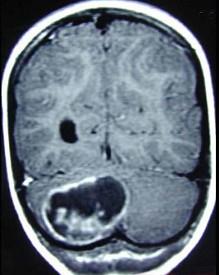

问题 男性,39岁,头痛、步态不稳3个月。查体:神清,双侧视乳头水肿,右侧轮替动作不能。周围血象红细胞增多,B超发现右肾有一囊性肿物,头颅CT发现右小脑半球囊性占位性病变(如图所示)。其病变性质最可能是()

选项 A.转移瘤 B.血管网状细胞瘤 C.上皮样囊肿 D.脑脓肿 E.星形细胞瘤

答案 B